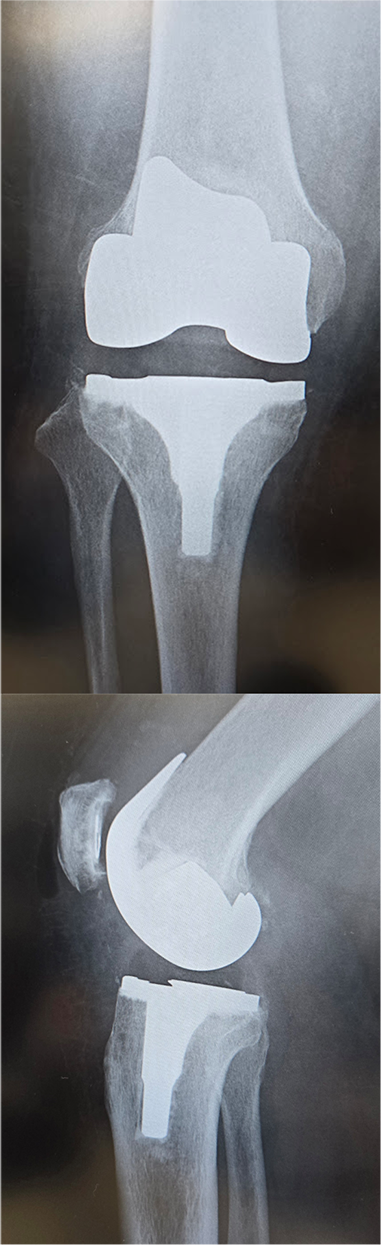

〈手術後のレントゲン〉(正面・側面)

右膝

左膝

当院にて人工ひざ関節全置換術(TKA)を施行。両側の手術を同時に行いました。両側同時手術の場合でも入院期間は片側手術の場合と大きく変わらず(プラス1週間程度)、麻酔も1回で済むために身体的、経済的な負担の軽減を期待できます。また両ひざが同程度に悪いケースも少なくなく、同時に行うことで左右のバランスが良くなるためにリハビリをスムーズに進めることが可能となります。

*写真・動画はご本人の承諾を得て掲載しております。(執刀/撮影:森島)

*術後の経過には個人差があります。